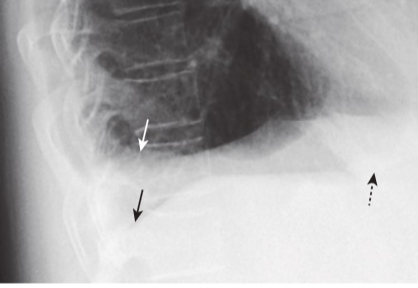

Pseudotumor in the minor fissure.

A, A sharply marginated collection of pleural fluid contained between the layers of the minor fissure produces a characteristic lenticular shape (solid black arrows in images A and B) that frequently has pointed ends on each side, where it insinuates into the fissure so that pseudotumors look like a lemon on frontal (A) or lateral (B) chest radiographs (dotted black arrow in [A] and dotted white arrow in [B]). Pseudotumors always occur along the course of the minor or major fissure, which helps to distinguish them from an actual tumor of the lung.